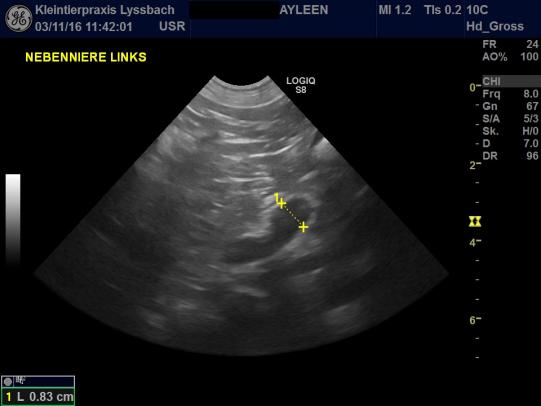

Der körperliche Untersuch von Ayleen verläuft unauffällig. Für das Leitsymptom "PU/PD" (Polyurie/Polydipsie = zuviel Urin absetzen/zuviel trinken) gibt es eine ganze Reihe von Ursachen, weshalb weitere Abklärungen angestellt werden: Eine Blutentnahme zeigt, dass Ayleen weder an einer Zuckerkrankheit, noch an einem Nierenproblem oder einer Erhöhung des Calciumspiegels leidet. Einzig ein spezifischer Leberwert ist erhöht, welcher häufig bei einer Nebennierenüberfunktion ansteigt. Ein entsprechender Test zeigt, dass die Nebennieren von Ayleen viel zuviel Cortison produzieren. Mittels Ultraschall werden die Nebennieren vermessen - die linke Nebenniere ist leicht vergrössert; die rechte Niere ist grössenmässig im oberen Grenzbereich. Es besteht der dringende Verdacht, dass Ayleen an einem sogenannten "hypophysären Cushingsyndrom" leidet - bei dieser Krankheit scheidet ein kleiner Tumor in der Hirnanhangsdrüse zuviel Steuerungshormon ACTH aus, welches die Nebennieren viel zuviel Cortison bilden lässt. Diese Form des Cushingsyndromes ist deutlich häufiger als die Nebennierenform, bei der ein Nebennierentumor zuviel Hormon produziert (siehe Fall des Monats Nr. 83 ).